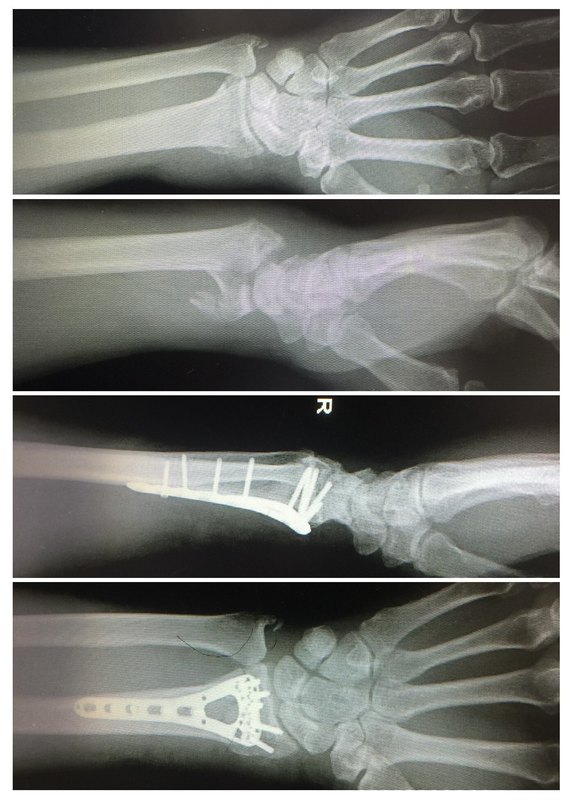

腕关节镜下涉及关节面C型桡骨远端骨折复位固定技巧

桡骨远端骨折,尤其C2-3型骨折,涉及关节面,关节面可能有>1mm的台阶,关节腔内可能有碎骨块,可能合并舟月韧带,三角纤维软骨复合体等损伤。应用腕关节镜,不仅能精准复位关节面骨块,减少关节面台阶,清除碎骨块,更重要的是,确诊舟月韧带,尺腕韧带,TFCC等合并损伤,并同时在镜下修复损伤的韧带,减少术后并发症的发生。